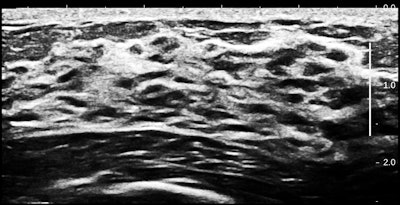

The following unusual case will give us a good clue about another potential facet of ultrasound breast screening.

All images courtesy of Dr. Jason Birnholz.This finding goes by the term "nipple dichotomy," and in this case it was unilateral. This is a duplication anomaly involving the entire breast, not a superficial cosmetic concern.

Inside the breast, there is twice the number of gland cells as in an ordinary breast. As you can see, parenchyma fills the space from the chest wall muscle to a relatively thin rim of fat. There is also duct ectasia.